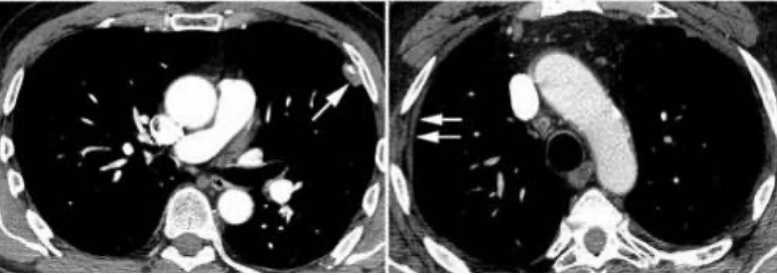

Dans cette image une ... est atteinte, ce qui est caractéristique des micronodules à distribution ...

le diagnostic probable est une ...

(grande) scissure, périlymphatique, sarcoïdose